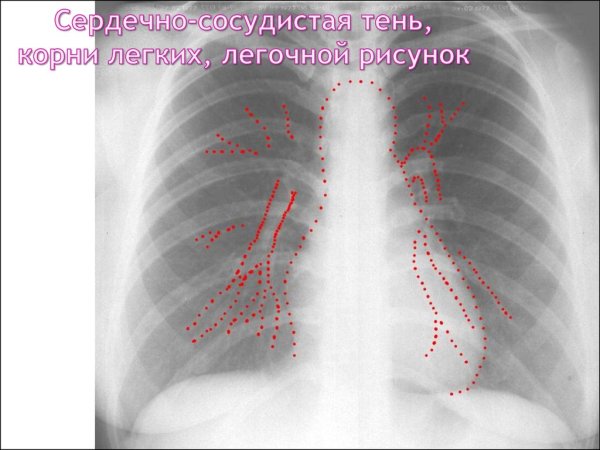

Усиление легочного рисунка на рентгене